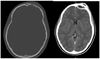

A 5-year-old boy is referred for evaluation of facial asymmetry. His parents report that they have noticed asymmetry since birth and believed it would improve with time, but it has not. The patient has no history of surgery or physical therapy. On physical examination, the physician notes skull asymmetry and facial asymmetry, including the orbits; there is no obvious neck tilt. A CT scan of the head is most likely to show which of the following?

The correct response is Option A.

Since the early 1990’s when positional deformational cranial deformities were first identified with the “back-to-sleep” campaigns, they have now become the most common etiology of cranial and facial asymmetry. Prior to that time, torticollis was the most common cause. Craniosynostosis is a much less frequent cause and occurs in the following order of decreasing frequency: unicoronal, lambdoid, zygomaticotemporal. Correct identification of most of the causes of this clinical constellation of findings can be made on clinical examination, but most would still get a CT scan to verify the diagnosis and rule out associated anomalies except for torticollis, which is always a clinical diagnosis.